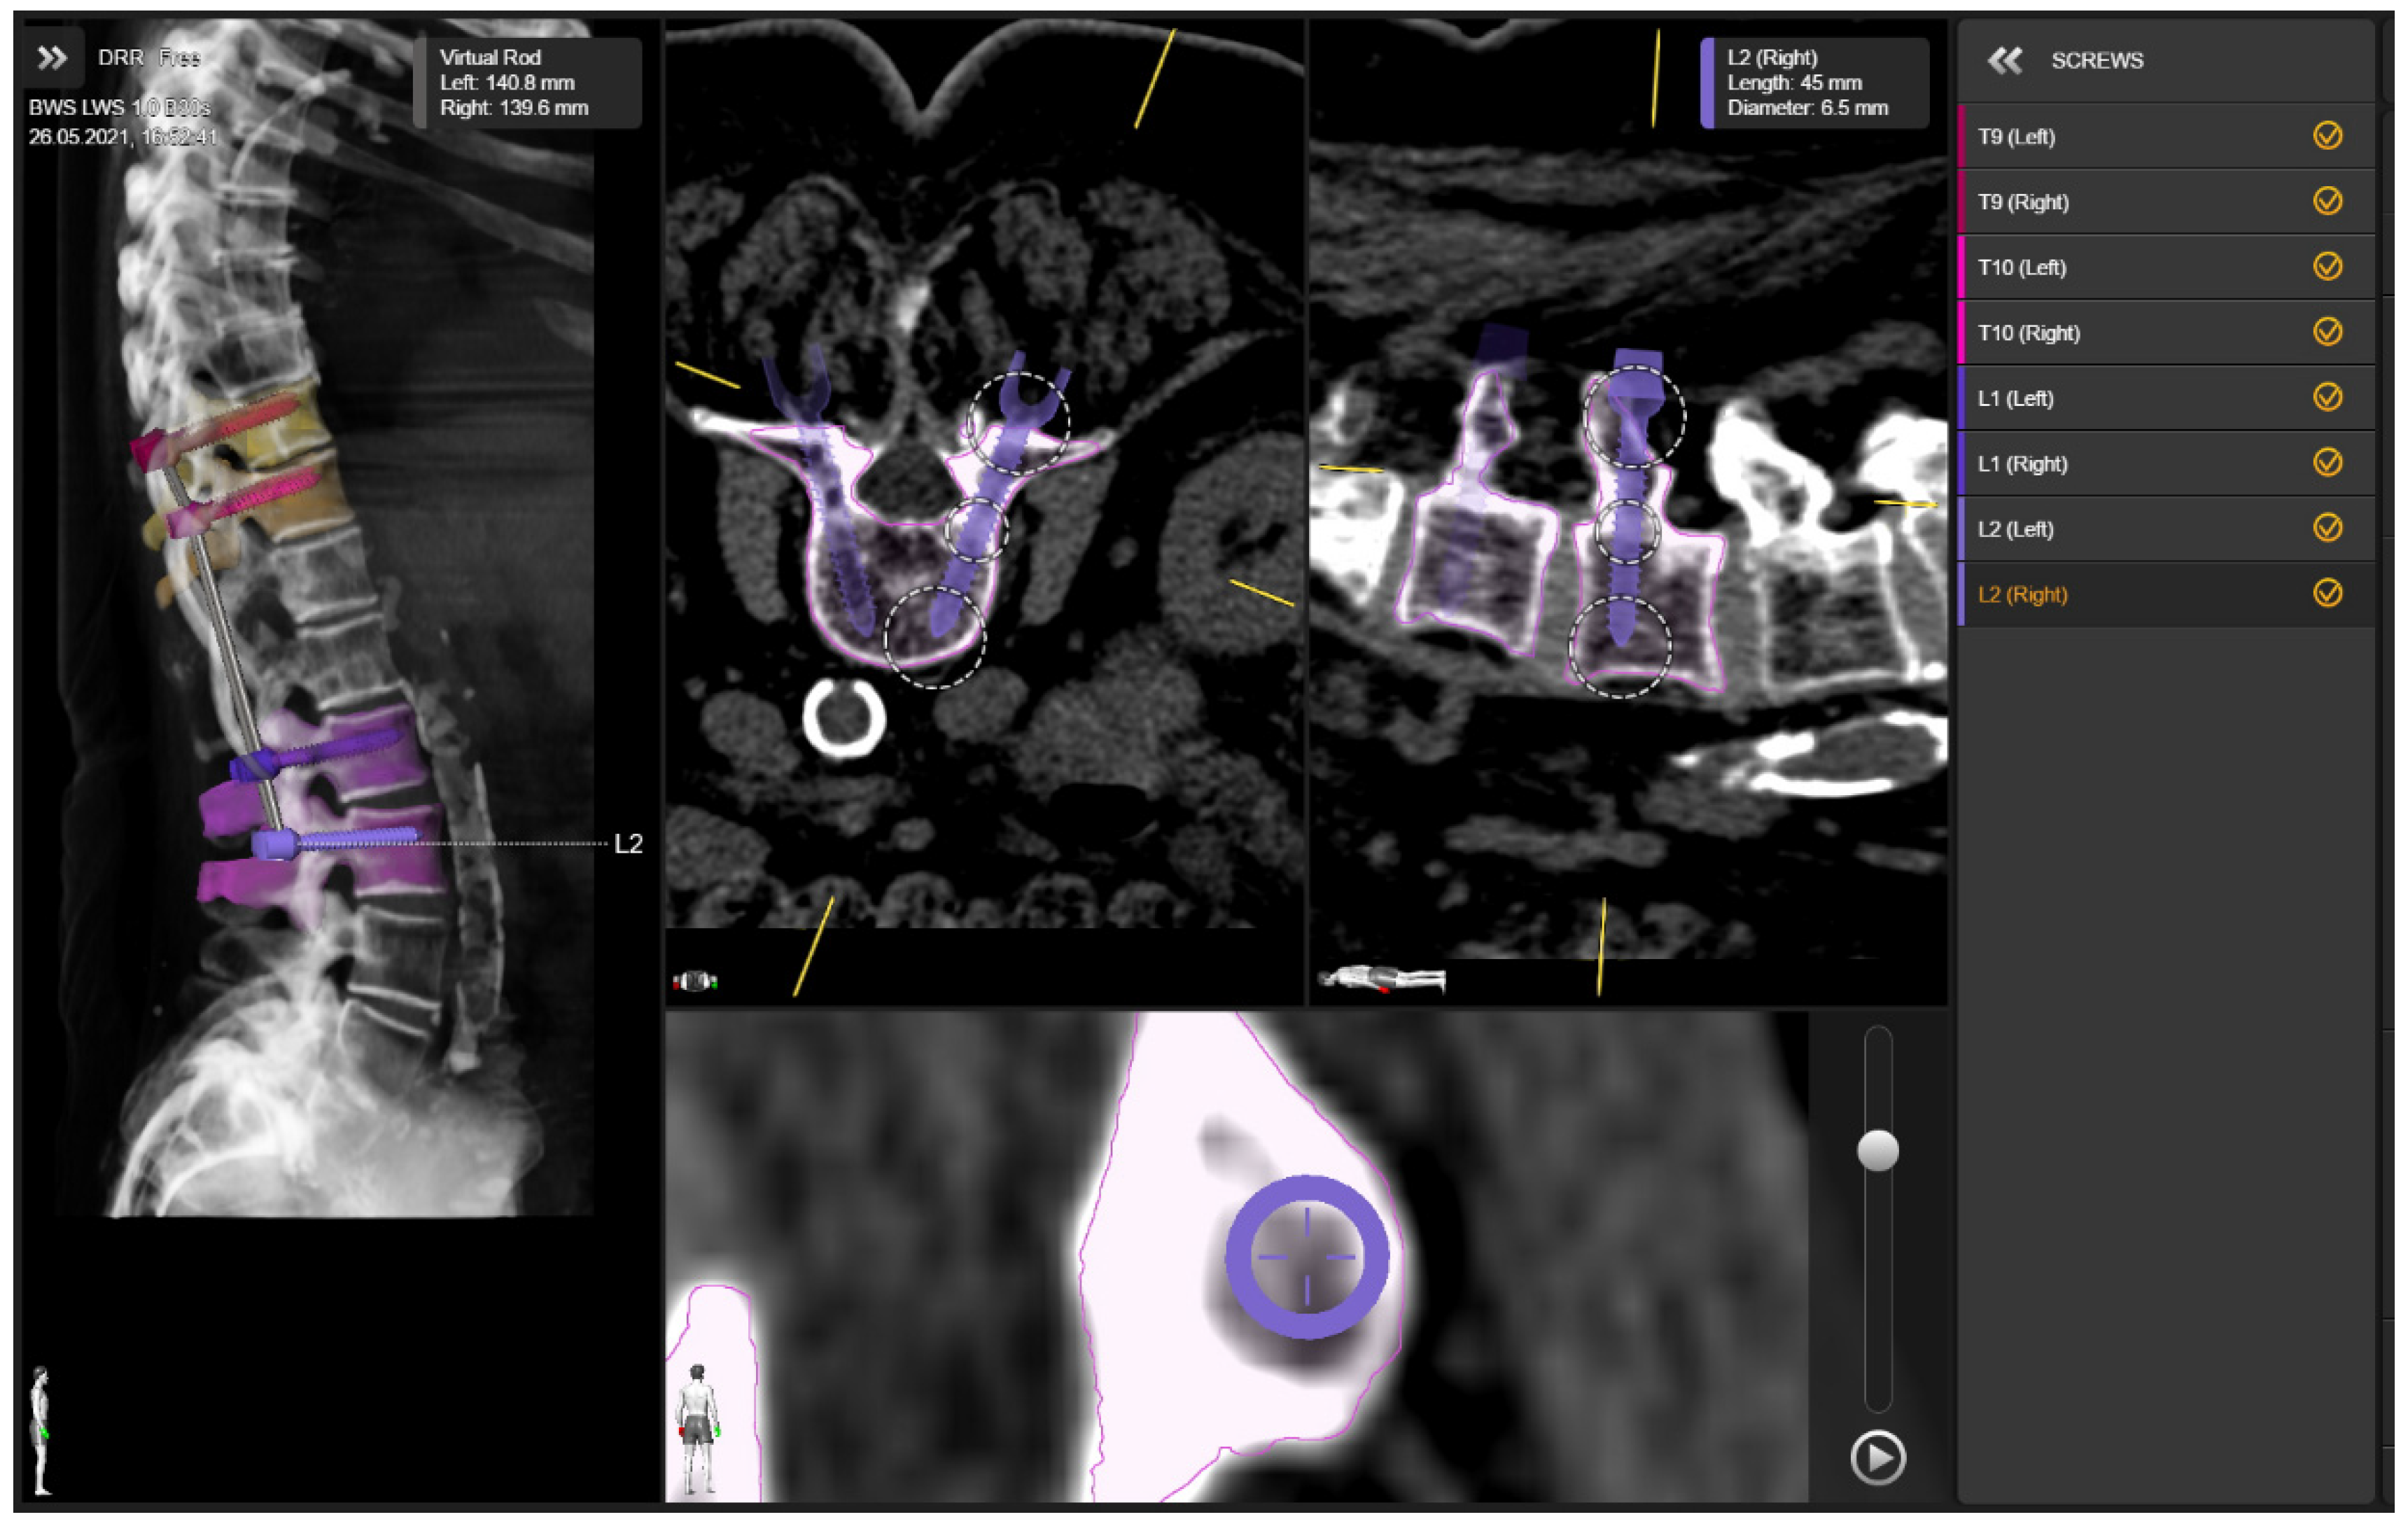

- Deviation of preplanned trajectory from actual pedicle screw position—offset of the screw compared to preplanned trajectory (degrees to medial/lateral): mean deviation in entry point, the average deviation from the tip of the screw, and angular deviation. Deviations were determined using an image-overlay analysis to compare preoperative CT imaging with preplanned screw trajectories to a true screw position on intraoperative, control CT imaging (Figure 6). The mean deviation of entry point and the average offset from the tip of the screw were measured in the axial plane by determining the perpendicular distance of the midline of the planned screw versus the midline of the actual screw position; this latter line was drawn manually in the software as a best estimate on the slice with the widest screw diameter. Angular deviation was measured by determining the angle of the midline for the planned screw versus the midline of the actual screw position in the lateral plane.